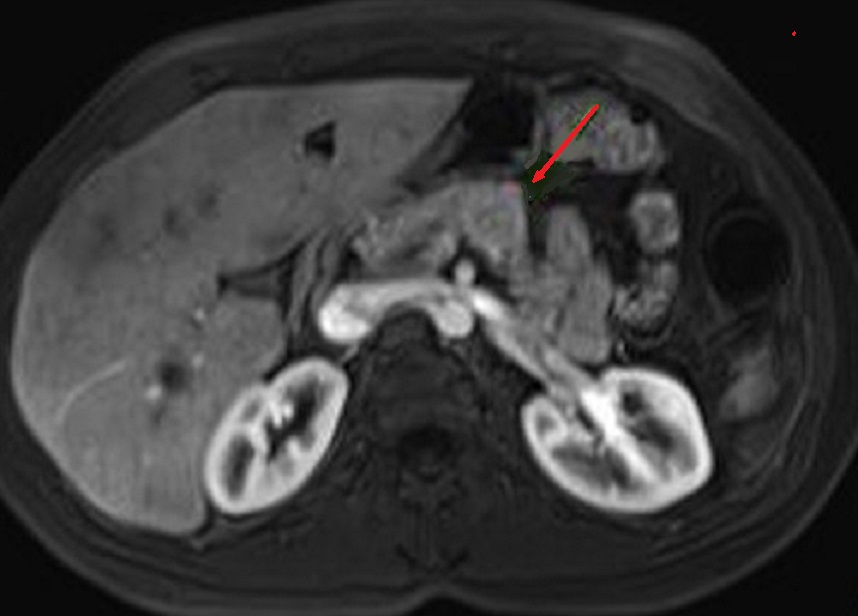

L'IRM : C'est technique

avait une sensibilite resemble la TDM . Aspect radiologique

IRM d'une tumeur endocrine du pancreas est image hypointense

sur T1 ( relative avec parenchyme du pancreas ) et

hyperintense sur les coupes pondere T2 . Sur les coupes T1

avec Gadolinium intraveineuse ( Gd ) le tumeur est

hypervascularise et hypersignal .

Meme cas en coupe IRM ponderation T2 (

fleche rouge . La tumeur devient hypersignal que le

parenchyme du pancreas . Ce que se donne comme une

technique d'utilise pour decouverte des petites

tumeurs |

Un autre cas de tumeur endocrine du corps

pancreas . Aspect radiologique est un nodule

hyperdense a ponderation T2 . Image radiologique IRM

de ponderation T2 en coupe axiale . |